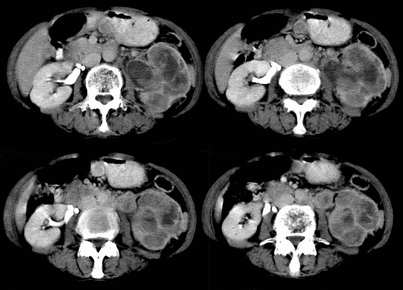

病患,女,69岁,左侧腰部不适,偶感疼痛2个月余,无化验室检查,行彩超发现左侧肾区实质性肿物,后行ct检查,结果同上。

左肾不规则软组织肿块,内见低密度坏死区,与正常肾实质分界不清,左肾明显增大,增强呈不规则条索状强化,肾盂及左输尿管上段扩张。肾周脂肪层受侵、模糊。印象:典型左肾癌。

平扫,表现为肾实质肿块,呈分叶状,肿块密度不均,内有不规则低密度区(陈旧性出血?坏死?)有的似呈囊性,增强明显不均一强化,与肾实质相比呈相对低密度的不均一肿块,肾周脂肪间隙可见,肾前筋膜未见增后,肾血管及腹主动脉旁未见肿大淋巴结影

三期抓的不错,典型的肾癌,且已累及肾盂及左输尿管上段

左肾癌累及左输尿管,左肾静脉无受累征象。